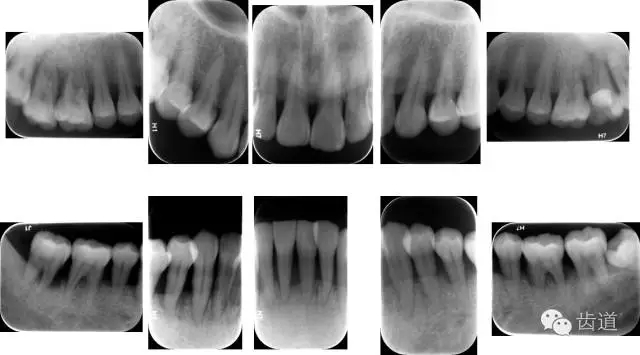

6、輔助檢查

X線:根尖片、曲面斷層片(牙槽嵴頂,水平垂直吸收,程度)

21.webp.jpg

22.webp.jpg

23.webp.jpg